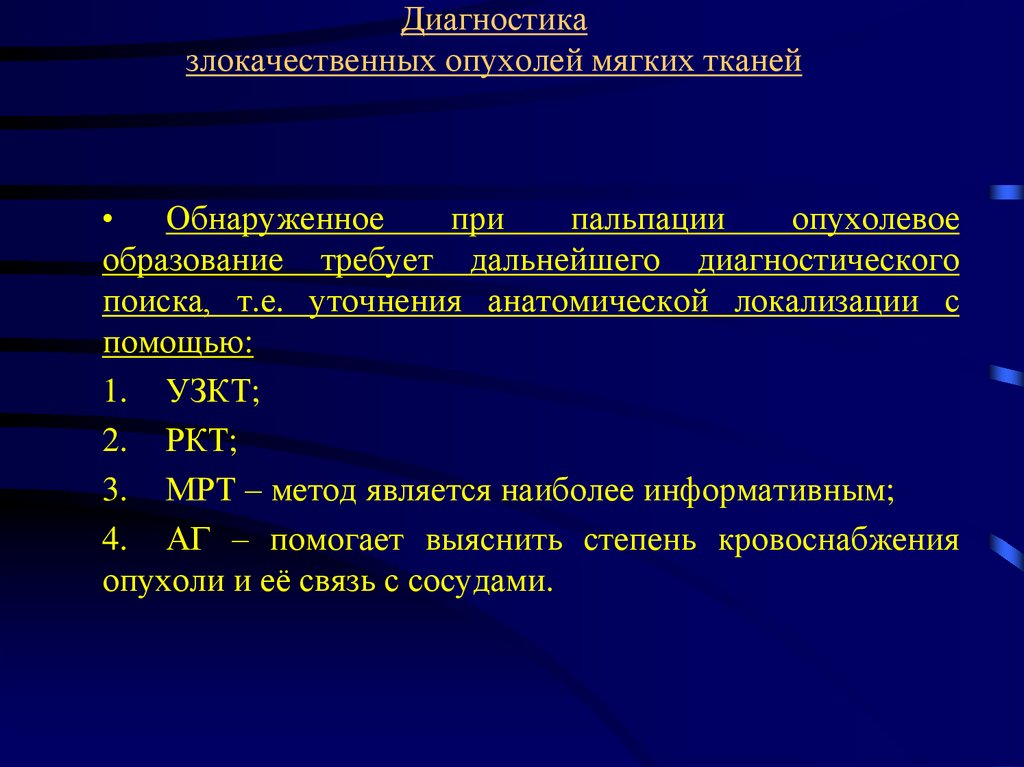

Понятие онкологической настороженности. Онкологическая настороженность в стоматологии презентация. 7 «Сигналов» злокачественной опухоли. Настороженность по онкологии. Алгоритм диагностики опухолей. Методы диагностики опухолей костей. Методы выявления опухоли. Методы диагностики злокачественных опухолей.

Алгоритм диагностики опухолей. Методы диагностики опухолей костей. Методы выявления опухоли. Методы диагностики злокачественных опухолей. Методы диагностики опухолей. Метод диагностики опухолей. Методы выявления опухоли. Методы диагностики злокачественных опухолей.

Методы диагностики опухолей. Метод диагностики опухолей. Методы выявления опухоли. Методы диагностики злокачественных опухолей.